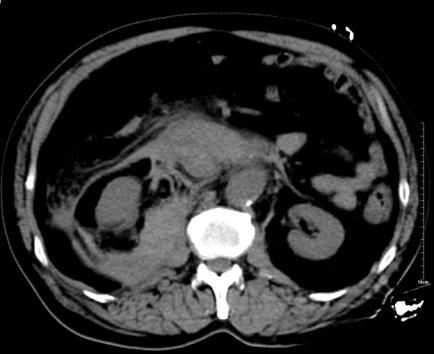

肝脏大小正常、形态规则、包膜完整、各叶比例协调,肝左外叶见以点状密度增高影,肝内胆管和胆总管未见扩张,胆囊形态自然,大小正常,其内未见异常密度影,胰腺形态、大小未见明显异常,脾脏未见增大征象,包膜完整,右肾周及腹主动脉周围,中上腹腔见条带状及片状稍低密度影,形态欠规整。

增强后:腹主动脉下段至左右髂总动脉上端明显扩张,最宽处约6.8cm,上下径约为13cm,成瘤样改变,边界清楚,形态规整。